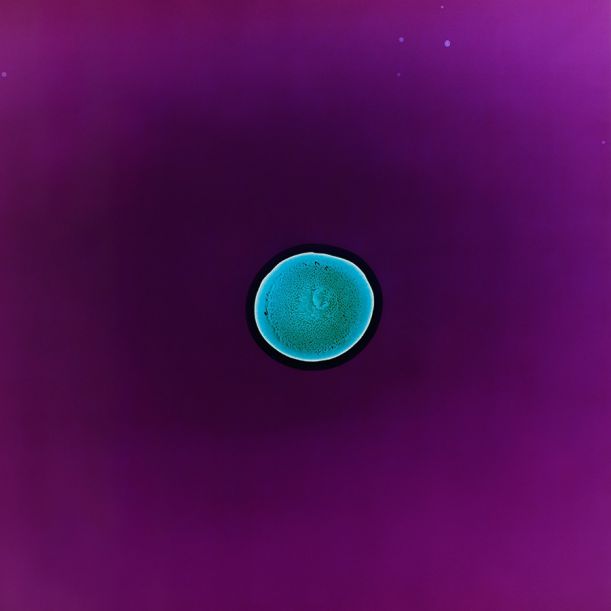

5. MDMA

Čistá krystalická extáze – mnohem silnější než barevné pilulky. Budete se sice cítit skvěle, i když chvílemi až tak, že to půjde těžko ustát, ale připravit se můžete i na sucho v ústech, skřípání zubů, svírání čelistí, nevolnost, pocení, cukání svalů i očí, eventuálně křeče, dehydrataci a následnou depku.